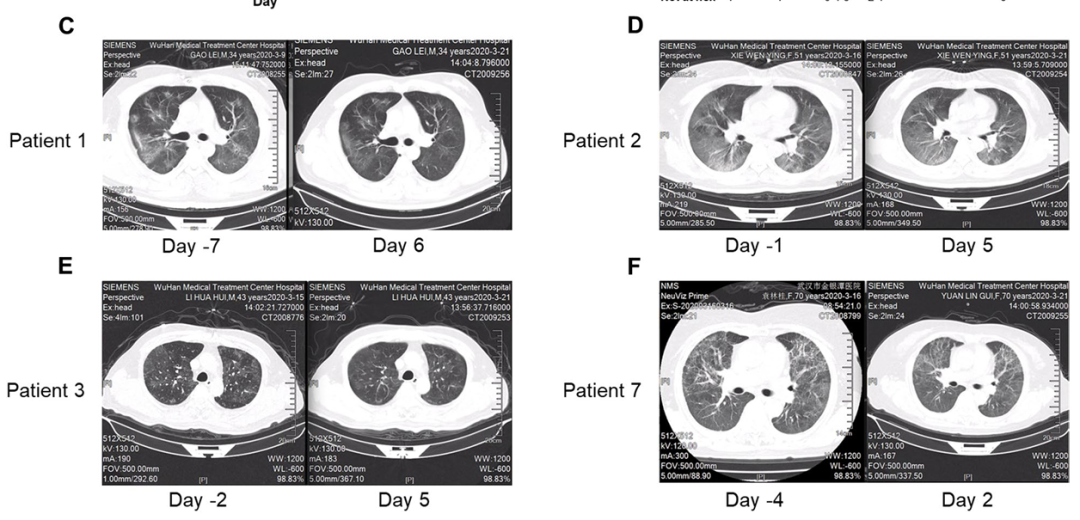

2a期临床试验:纳入了7例重症新冠病毒(COVID-19)肺炎患者,接受连续5天的外泌体雾化治疗。

结果显示,所有患者对于外泌体雾化治疗的耐受性良好,完成雾化治疗后大多数患者的临床症状和CT图像评分得到改善,淋巴细胞减少症呈改善趋势,其中有4名患者的肺部病灶消退尤为明显。

图C-F:COVID - 19患者吸入haMSC-Exos前后胸部CT扫描的变化。

其中,图E为一名70岁患者治疗前后的胸部CT图像,与治疗前相比,接受外泌体雾化治疗后CT图像上肺部大片浸润及磨玻璃影消失。